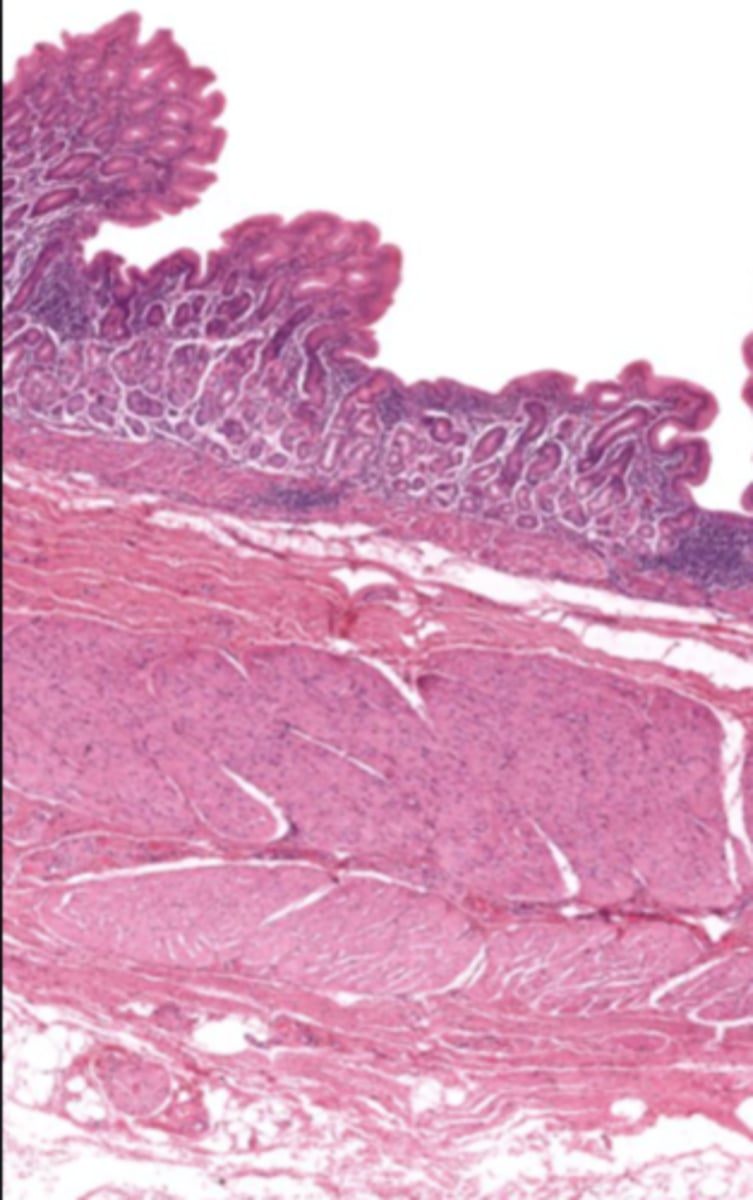

gallbladder (histology)

gallbladder

this tissue's wall structures/layers are different than the rest of the organs

simple columnar epithelium

lumen (gallbladder)

mucosa (gallbladder)

mucosal epithelium (gallbladder)

lamina propria (gallbladder)

muscularis mucosa and submucosa

gallbladder tissue does not have _______ and ______

muscularis externa (gallbladder)

serosa/adventitia (gallbladder)